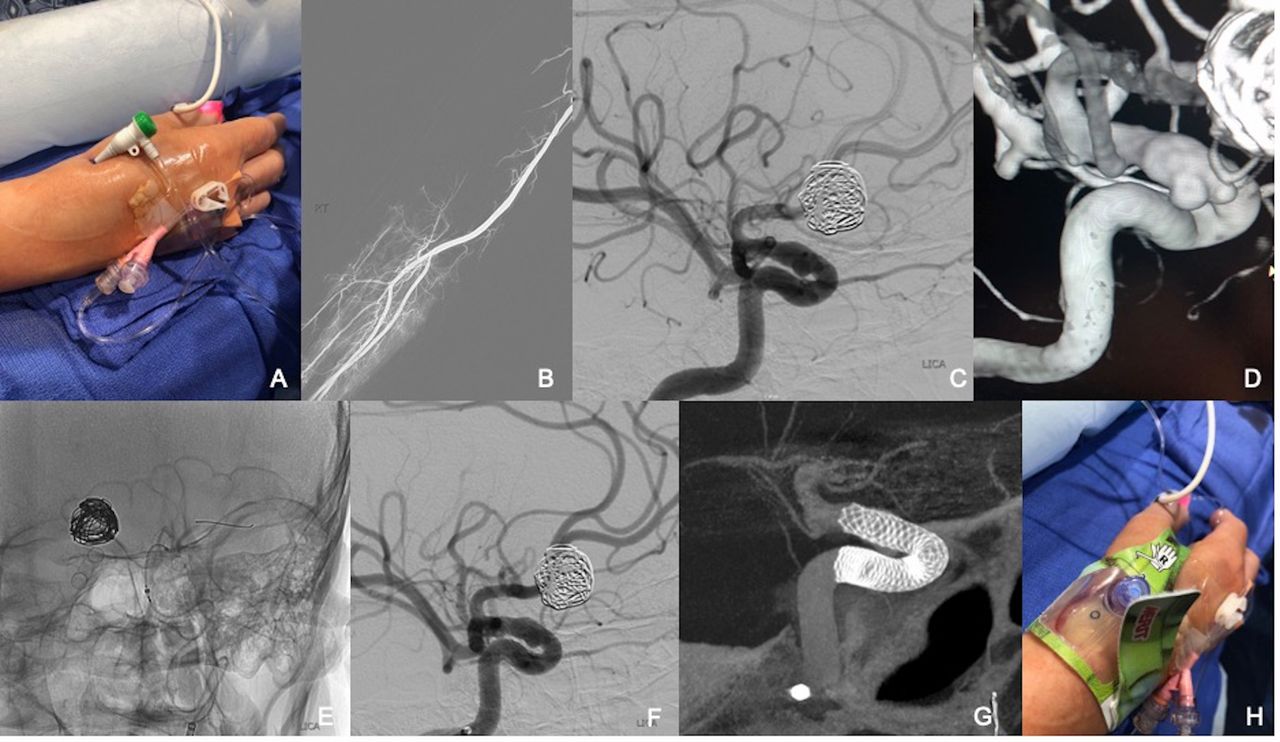

Distal radial access in the anatomical snuffbox for neurointerventions: a feasibility, safety, and proof-of-concept study

Journal of NeuroInterventional Surgery, Published Online First: 08 January 2020. doi: 10.1136/neurintsurg-2019-015604

According to Neurointerventional Radiology Division Chief Ajit Puri, MD "this recent publication which is the first and largest series in the world of patients treated for minimally invasive endovascular Neurointerventional procedures from the artery of the hand (distal radial artery (snuffbox) is now published. This takes a minimally invasive access with a newer novel approach to new heights. Patients love it - a brain aneurysm fixed via the artery of the hand."

Distal radial access in the anatomical snuffbos for neurointerventions